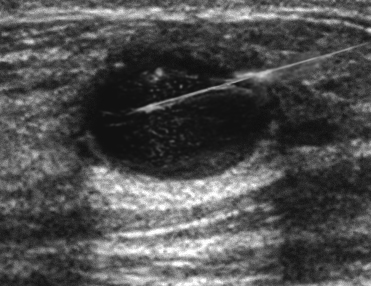

core-needle biopsy - breast cancer

Biopsy may be performed with imaging to help localize the lesion.

The typical steps involved in breast biopsy procedures include localization of the suspicious area through imaging techniques such as ultrasound, mammography, or MRI. Different guidance methods may be employed depending on the location and characteristics of the lesion. For example, an ultrasound-guided biopsy is used for lesions that are easily visible on ultrasound. This involves the use of real-time ultrasound imaging to guide the needle to the correct location.